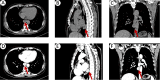

To our knowledge, this is the first reported case of coexisting esophageal schwannoma and gastric fundus gastrointestinal stromal tumor (GIST). This case report describes the diagnostic and treatment process of a patient with esophageal schwannoma who also had a concurrent gastric fundus GIST and was presented to Hebei General Hospital (Hebei, China) in October 2024. The association between the pathogenesis of the two types of submucosal gastrointestinal tumors is unclear, with limited existing evidence in the literature. The esophageal schwannoma was misdiagnosed as a leiomyoma preoperatively, which prompted us to seek new diagnostic modalities to differentiate gastrointestinal submucosal lesions (leiomyomas, GISTs, and schwannomas). Surgical resection is considered the optimal treatment for esophageal schwannoma. The patient underwent a right single-port thoracoscopic esophageal tumor resection and recovered well, subsequently being discharged smoothly from the hospital.